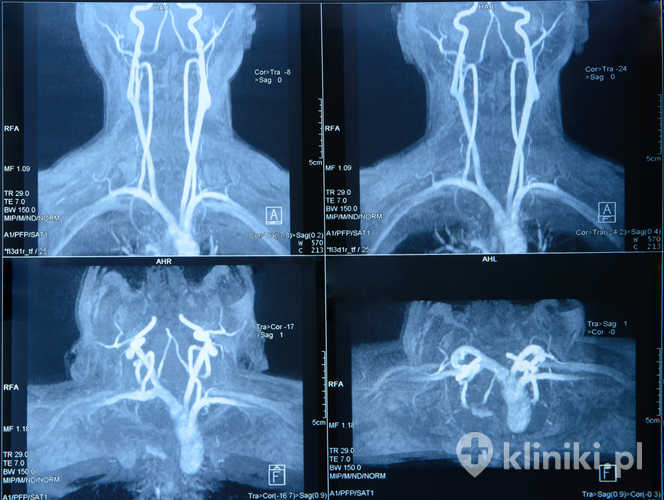

W codziennej praktyce klinicznej do zamykania naczynek na szyi szeroko wykorzystuje się dedykowane lasery naczyniowe (np. KTP 532 nm, PDL 585–595 nm, Nd:YAG 1064 nm). Dobór długości fali zależy od średnicy i głębokości naczynia oraz fototypu skóry.

IPL (który nie jest laserem) bywa skuteczny przy drobnych, płytkich teleangiektazjach, natomiast głębsze, szersze naczynia częściej wymagają fal dłuższych (np. 1064 nm) i/lub kilku sesji. Stosuje się także systemy chłodzenia kontaktowego lub zimnym powietrzem w celu poprawy komfortu i bezpieczeństwa.

Obecnie zarówno chirurgia plastyczna, jak i medycyna estetyczna dysponuje kilkoma technikami pozwalającymi zamykać rozszerzone naczynia umiejscowione na szyi w celu uzyskania pożądanych efektów, zarówno terapeutycznych, jak również estetycznych. Współcześnie drobne naczynia krwionośne mogą być zamykane za pomocą metody elektrokoagulacji lub techniką laserową (na twarzy i górnej części ciała) oraz skleroterapią (na nogach).

Na ilość zastosowanych zabiegów ma wpływ rodzaj zmiany, jej wielkość i rozmieszczenie, jest to często sprawa indywidualna. Laserowe zamykanie naczyń IPL (ang. Intense Pulsed Light) dotychczas jest najbardziej skuteczną, nowoczesną terapią pozwalającą na eliminację rozszerzonych naczyń krwionośnych zlokalizowanych na szyi i uzyskanie jak najlepszych efektów estetycznych.

Jest to metoda lecznicza dla pacjentów w każdym wieku. Naczynia drobniejsze, których nie wychwyci urządzenie IPL, usuwa się za pomocą tego samego mechanizmu działania, z zastosowaniem urządzenia RPL (ang. Variable Pulsed Light) emitującym wiązki światła o zdecydowanie szerszym spektrum.

Jak sama nazwa wskazuje, zabieg laserowego zamykania naczyń, opiera się na użyciu lasera w celu uzyskania oczekiwanych efektów. Światło lasera aktywuje naturalny proces niszczenia ścian naczyń krwionośnych.

Wiązka laserowa o odpowiedniej długości ulega pochłonięciu przez czerwony barwnik krwi, którym jest hemoglobina. W wyniku procesu termolizy produkowana jest niezbędna energia cieplna.

Woda znajdująca się w tkance zostaje odparowana, a naczynie krwionośne wysusza się, obkurcza i obumiera. Zniszczone elementy zostają usuwane przez organizm w procesach metabolicznych.

Aby zabieg był w pełni skuteczny należy dobrać odpowiednią długość fali świetlnej. Właściwe jego wykonanie poprzedzone jest testem, pozwalającym wyznaczyć optymalne parametry energii lasera, aby przy jak najmniejszej ilości uzyskać jak najlepszy efekt.

Pozwala to na zamknięcie naczyń krwionośnych zlokalizowanych na szyi różnej wielkości i zlokalizowanych na różnej głębokości. Długość zabiegu zależy od wielkości zmiany, na którym jest on wykonywany oraz wrażliwości pacjenta.